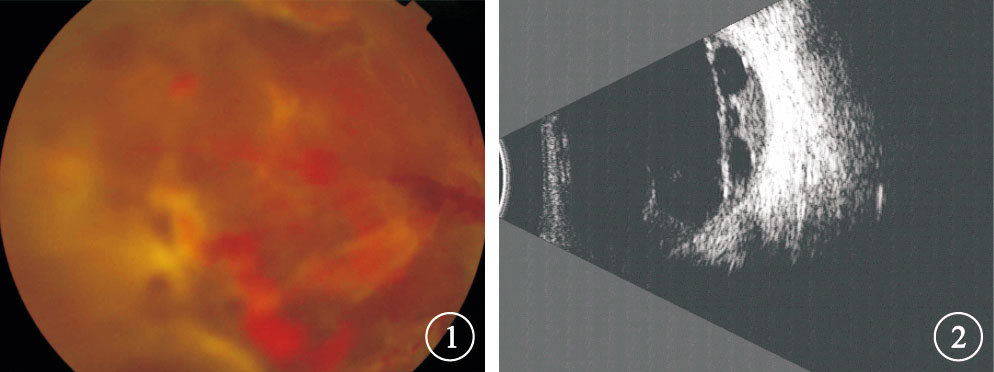

均行最佳矯正視力(BCVA)、眼壓、裂隙燈顯微鏡、間接檢眼鏡、B型超聲、眼底彩色照相、光相干斷層掃描檢查。患眼平均BCVA 0.03±0.25。數指及以下者18只眼,占36.0%;<0.1者15只眼,占30.0%;0.1~0.3者16只眼,占32.0%;>0.3者1只眼,占2.0%。BCVA數指及以下者18只眼中,光感者3只眼,手動者4只眼,數指者11只眼。TRD累及黃斑16只眼,其中廣泛視網膜脫離4只眼(圖 1,2);未累及黃斑34只眼。TRD累及黃斑的16只眼BCVA為光感~0.05,其中數指及以下9只眼;平均BCVA 為0.01±0.36。未累及黃斑的34只眼BCVA為手動~ 0.5,其中數指以下9只眼;平均BCVA為0.05±0.30。兩者BCVA比較,差異有統計學意義(t=-4.841,P<0.01)。

患眼彩色眼底像。后極部大面積纖維增生膜伴視網膜前出血??圖 2 圖 1患眼B型超聲像。玻璃體內條狀光帶,與視盤相連,光帶呈中強回聲,光帶下可見密集點狀回聲

均行最佳矯正視力(BCVA)、眼壓、裂隙燈顯微鏡、間接檢眼鏡、B型超聲、眼底彩色照相、光相干斷層掃描檢查。患眼平均BCVA 0.03±0.25。數指及以下者18只眼,占36.0%;<0.1者15只眼,占30.0%;0.1~0.3者16只眼,占32.0%;>0.3者1只眼,占2.0%。BCVA數指及以下者18只眼中,光感者3只眼,手動者4只眼,數指者11只眼。TRD累及黃斑16只眼,其中廣泛視網膜脫離4只眼(圖 1,2);未累及黃斑34只眼。TRD累及黃斑的16只眼BCVA為光感~0.05,其中數指及以下9只眼;平均BCVA 為0.01±0.36。未累及黃斑的34只眼BCVA為手動~ 0.5,其中數指以下9只眼;平均BCVA為0.05±0.30。兩者BCVA比較,差異有統計學意義(t=-4.841,P<0.01)。

患眼彩色眼底像。后極部大面積纖維增生膜伴視網膜前出血??圖 2 圖 1患眼B型超聲像。玻璃體內條狀光帶,與視盤相連,光帶呈中強回聲,光帶下可見密集點狀回聲